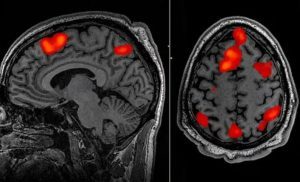

Un nuevo sistema de inteligencia artificial puede reconstruir los pensamientos de una persona con gran exactitud a partir del escaneo de su cerebro con fMRI.

Metidos cada uno en un escáner de resonancia magnética funcional, tres voluntarios escucharon pacientemente varias historias –en concreto, de un podcast famoso en Estados Unidos–. Mientras, un modelo de lenguaje (LLG, siglas en inglés de Large Language Model), el GPT-1, al que los investigadores se refieren como "descodificador", iba analizando sus patrones de actividad cerebral en distintas regiones del córtex, buscando correlaciones entre esos datos y el contenido de los mensajes que estaban escuchando. Durante 16 horas –¡no seguidas!– entrenaron al programa para que fuera capaz de traducir la forma en que el cerebro reproducía las historias mientras las escuchaba.

En la siguiente fase del experimento, los voluntarios escuchaban una nueva historia, también dentro del escáner, mientras el decodificador iba generando texto solo a partir de la actividad cerebral registrada por las imágenes neuronales. El éxito fue sorprendente: alrededor del 50% de las veces, el mensaje producido era semánticamente parecido, cuando no idéntico, al original. Lo mismo ocurría cuando, en vez de reproducir un audio, se les ponía un vídeo corto en silencio. El programa era capaz de crear sinopsis de su contenido, solo a partir del escáner cerebral.

¿Funcionaría también para adivinar el pensamiento del voluntario, sin que este escuchara nada? Los investigadores comprobaron que sí. En la siguiente prueba, se les pedía a los participantes que imaginaran una idea o un mensaje bajo el escaneo del fMRI. Y el decodificador fue, de nuevo, capaz de transcribir la actividad cerebral a palabras con bastante precisión en cuanto al contenido semántico.

Utilizando un programa basado en Inteligencia Artificial (IA) y particularmente el programa GPT-1, una computadora logró decodificar y describir la esencia de las historias que escuchó él y los tres participantes iniciales en el experimento de prueba de concepto, simplemente mirando sus resonancias magnéticas funcionales. Según sus resultados, publicados en la revista científica Nature Neuroscience, este descodificador que han llamado “semántico” fue capaz también de verbalizar lo que pensaban y observaban mientras veían cine mudo.

Escuchar esas líneas estimuló la actividad cerebral, las neuronas se dispararon y consumieron el oxígeno en su sangre. A medida que la sangre desoxigenada fluía de regreso a sus pulmones y corazón, el imán captó su señal, decodificando qué partes de su cerebro estaban procesando lo que había escuchado. Los investigadores han desarrollado el primer método no invasivo para determinar la esencia del habla imaginada, presentando una posible salida de comunicación para las personas que no pueden hablar.

El decodificador puede reconstruir el habla utilizando datos de escaneo fMRI.

Los expertos utilizaron el programa GPT-1. Este modelo de lenguaje, desarrollado por el laboratorio de inteligencia artificial OpenAI, usa aprendizaje profundo para generar texto. En esta investigación, lo entrenaron con las imágenes fMRI del cerebro de tres personas a las que hicieron oír 16 horas de audios de un podcast del New York Times y del programa The Moth Radio Hour, logrando hacer corresponder lo que veían con su representación en la cabeza. La idea es que, cuando volvieran a oír otro texto, el sistema pudiera ir anticipándolo basándose en los patrones de lo ya aprendido.

El decodificador podría reconstruir el habla con una precisión asombrosa mientras las personas escuchaban una historia, o incluso imaginaban una en silencio, utilizando solo datos de escaneo fMRI. Los sistemas de decodificación de idiomas anteriores requerían implantes quirúrgicos colocar una serie de electrodos directamente en el cerebro. Pero este último avance plantea la posibilidad de nuevas formas de restaurar el habla en pacientes que luchan por comunicarse debido a un accidente cerebrovascular o una enfermedad de la neurona motora.

Este descodificador recibió el nombre de semántico. Anteriores interfaces registraban la actividad cerebral en las áreas motoras que controlan la base mecánica del habla, es decir, los movimientos de boca, laringe o lengua. “Lo que pueden descodificar es cómo la persona está tratando de mover la boca para decir algo. Nuestro sistema funciona en un nivel muy diferente. En lugar de fijarnos en el ámbito motor de bajo nivel, trabaja en el nivel de las ideas, de la semántica, del significado.Por eso no registra las palabras exactas que alguien escuchó o pronunció, sino su sentido, explicó Huth. Para esto, aunque las resonancias registraban la actividad de varias zonas cerebrales, se centraron más en las relacionadas con la audición y el lenguaje. La continuación de las pruebas prosiguió en una docena de pacientes, siempre con buenos resultados.

El proceso de aprendizaje fue intensivo: se requirió al principio quetres voluntarios permanecieran acostados en un escáner durante 16 horas cada uno, escuchando podcasts. El decodificador fue entrenado para hacer coincidir la actividad cerebral con el significado utilizando un modelo de lenguaje grande, GPT-1, un precursor de ChatGPT. Más tarde, los mismos participantes fueron escaneados escuchando una nueva historia o imaginando contar una historia y el decodificador se usó para generar texto solo a partir de la actividad cerebral. Aproximadamente la mitad de las veces, el texto coincidía estrechamente, y a veces con precisión, con los significados previstos de las palabras originales.